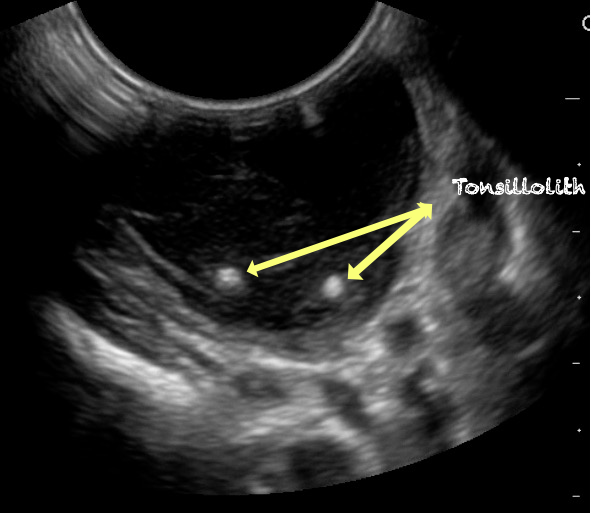

- Tonsillolith

- Calcified accumulated debris appears as millimeter sized hyperechoic lesions within the hypoechoic tonsillar parenchyma.

- Figure 44. Tonsillolith

Video 26. Tonsilloliths